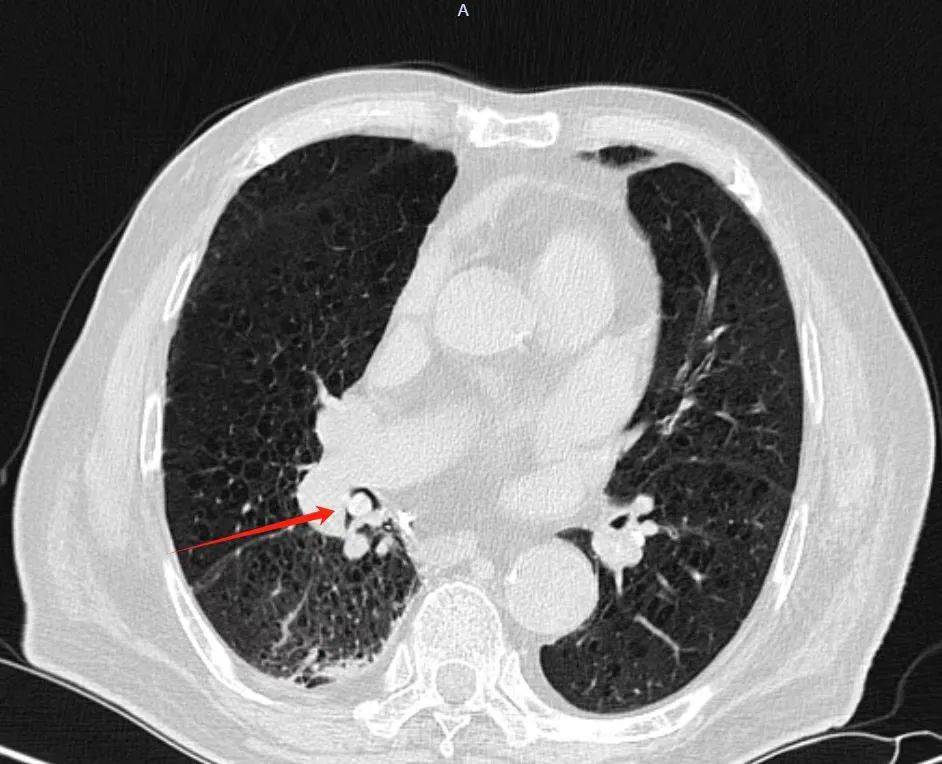

mds患者发热,ct见右肺下叶类圆形软组织影,考虑何因